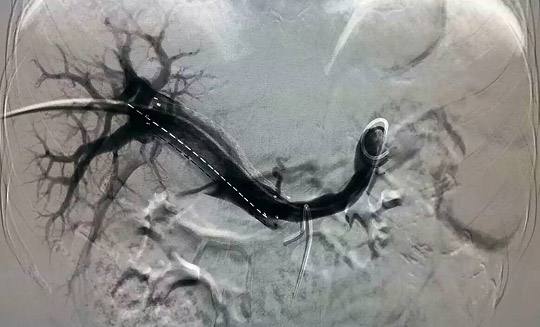

—腫瘤一科成功開展山東省首例支架+碘125粒子條治療門靜脈主干癌栓

2015年11月27日,在復旦大學附屬中山醫院介入科羅建鈞教授指導下,腫瘤一科張開賢主任帶領吳林霖、邢超、楊森等年輕醫生組成的介入團隊,成功地對一例原發性肝癌并門靜脈主干癌栓的患者實施了山東省首例支架+碘125-粒子條+肝動脈栓塞化療術,術后患者情況良好,目前正在進一步康復中。

門靜脈癌栓治療方法眾多,其中支架+碘125粒子條植入是近年來應用的一種新方法。支架可迅速開通門靜脈,恢復向肝血流,緩解門靜脈高壓,使肝功能恢復正常,但普通支架由于只有機械擴張作用而沒有抗腫瘤作用,術后很容易導致門靜脈堵塞,為解決這一難題,在植入門靜脈支架的同時植入碘125-粒子條,利用碘125放射性粒子發出的低能量伽馬射線持續殺傷腫瘤細胞,有效控制腫瘤生長,防止門靜脈再次堵塞,預防或推遲門靜脈再狹窄的發生,使門靜脈長時間保持通暢,為后續栓塞化療、消融治療等贏得時間,從而延長肝癌患者的生存期。